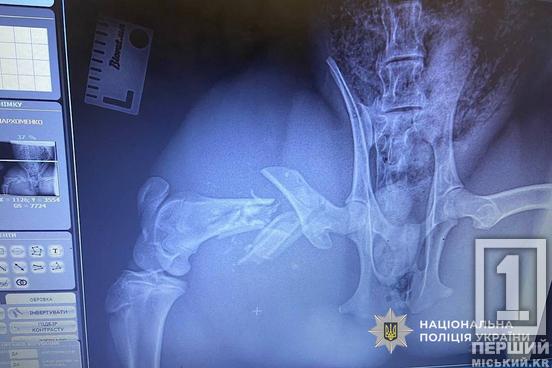

Дільничний офіцер, старший лейтенант Канан Кулізаде та співробітниця сектору реагування ПП, майор Аліна Полохало помітили лісову красуню поруч з трасою. Вони обережно перемістили тварину до авто та відвезли до ветеринарної клініки. Виявилося, що косуля дістала переломи. Про неї попіклувалися фахівці.